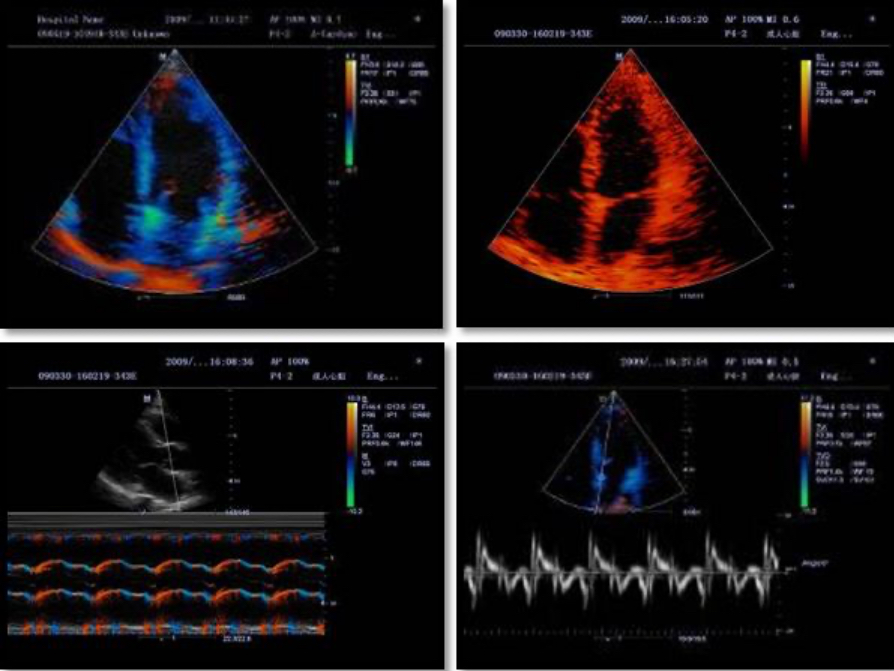

Tissue Doppler Imaging allows you to quantitatively evaluate local myocardial movement and function, providing complete TDI modes for faster and direct diagnoses.

Accurately evaluate myocardial motion at different phases, and simultaneously determine myocardial synchronization. High frame-rate providing you with accurate results.